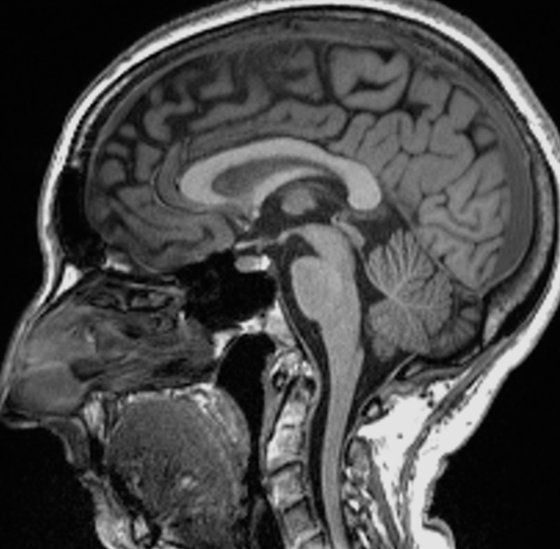

Shkencëtarët gjetën dallime të rëndësishme në skanimet MRI (imazhe me rezonancë magnetike) para dhe pas infeksionit. Edhe pas një infeksioni të lehtë, madhësia e përgjithshme e trurit ishte zvogëluar pak, me më pak lëndë gri në pjesët që lidhen me nuhatjen dhe kujtesën.

Studimi është publikuar në revistën Nature. Autori kryesor, profesor Gwenaelle Douaud nga Qendra Wellcome për Neuroimazhe Integrative, në Universitetin e Oksfordit, tha: “Ne po shikonim një infeksion në thelb të butë, kështu që për të parë se ne mund të shihnim vërtet disa ndryshime në trurin e tyre. Dallimi krahasuar me ata që nuk ishin infektuar ishte befasi”.

Madhësia e përgjithshme e trurit në pjesëmarrësit e infektuar ishte tkurrur midis 0.2 dhe 2%.

Pati humbje në lëndën gri në zonat e nuhatjes, të lidhura me nuhatjen dhe rajonet e lidhura me kujtesën. Ata që ishin shëruar së fundmi nga COVID-19 e kishin pak më të vështirë të kryenin detyra komplekse mendore. Por studiuesit nuk e dinë nëse ndryshimet janë të kthyeshme apo me të vërtetë kanë rëndësi për shëndetin dhe mirëqenien.

“Duhet të kemi parasysh se truri është vërtetë plastik, me këtë nënkuptojmë se mund të shërohet vetë, kështu që ekziston një shans shumë i mirë që me kalimin e kohës efektet e dëmshme të infeksionit të lehtësohen”, tha Prof Douaud.

Projekti UK Biobank ka ndjekur shëndetin e 500 mijë njerëzve për rreth 15 vjet dhe ka një bazë të dhënash të skanimeve të regjistruara para pandemisë, kështu që ofroi një mundësi unike për të studiuar ndikimet afatgjata shëndetësore të virusit.

Humbja më e madhe e lëndës gri ishte në zonat e nuhatjes, por është e paqartë nëse virusi sulmon drejtpërdrejt këtë rajon apo qelizat thjesht vdesin nga mungesa e përdorimit pasi njerëzit me COVID-19 humbasin shqisën e nuhatjes. Është gjithashtu e paqartë nëse të gjitha variantet e virusit e shkaktojnë këtë dëm.